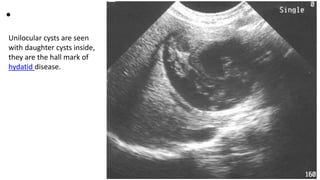

Unilocular cysts are seen

with daughter cysts inside,

they are the hall mark of

hydatid disease.

• Unilocular cysts areseen with daughter cysts inside, they are the hall mark of hydatid disease.